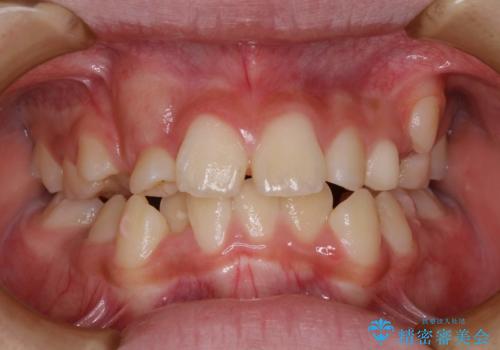

- 乳歯の晩期残存による永久歯の萌出遅延・過剰歯・萌出異常

など多くの問題を抱えていた。

乳歯がうまく抜けず、過剰歯が存在していたことにより、永久歯が位置異常をおこし、非常に複雑な状況となってしまっていました。